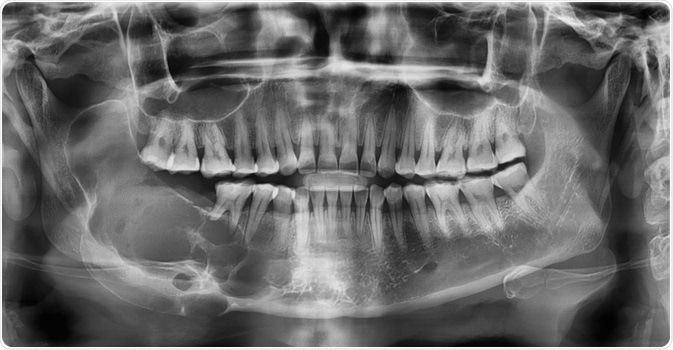

A combination of both clinical examination and an X-ray is commonly used to diagnose suspected ameloblastoma. Referral to an Oral and Maxillofacial Surgeon for a second opinion and confirmation of the diagnosis is fairly usual. Many ameloblastomas are discovered by chance at the dentist during ordinary dental operations or X-rays.

When a tumor seems to be an infection, causing discomfort and swelling in the jaw, it is usually treated with antibiotics. When antibiotics fail to ease the symptoms, a regular X-ray is taken to further check the symptoms, and the probable ameloblastoma is discovered. Further tests including CT scans, MRI scans, and a biopsy of the bone are used to confirm the presence of the tumor.